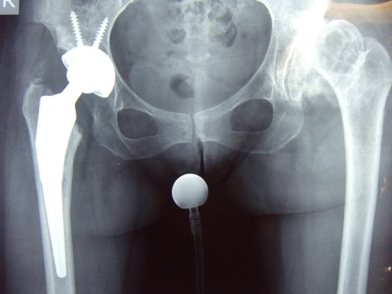

Στους ασθενείς με μη ανατεταγμένα ή μη επάλληλα ισχία και ανεπαρκή κάλυψη της μηριαίας κεφαλής οι οστετομίες διάσωσης της πυέλου, όπως η Chiari και η Shelf, έχουν εφαρμοστεί με σχετική επιτυχία ώστε να καθυστερήσουν την ανάπτυξη τελικού σταδίου οστεοαρθρίτιδας. Ωστόσο, όταν η τελευταία έχει πλέον εγκατασταθεί στην άρθρωση, η θεραπεία εκλογής παραμένει η ολική αρθροπλαστική ισχίου, η οποία μπορεί αξιόπιστα να απαλλάξει τους ασθενείς από τον πόνο και να βελτιώσει τη λειτουργικότητά τους, παρότι έχει συσχετισθεί γενικώς με μεγαλύτερα ποσοστά επιπλοκών σε σχέση με την αρθροπλαστική ισχίου για πρωτοπαθή οστεοαρθρίτιδα. Παρότι στα δυσπλαστικά ισχία αποφεύγεται η εφαρμογή ελάχιστα επεμβατικών τεχνικών αρθροπλαστικής, στην κλινική μας η Μέθοδος ASI χρησιμοποιείται ως τεχνική ρουτίνας και σε αυτές τις περιπτώσεις. Τέλος, η αρθροπλαστική επιφανείας του ισχίου, μία τεχνική αρθροπλαστικής με οικονομικότερη αφαίρεση οστού από την κεφαλή και τον αυχένα του μηριαίου, έχει περιγραφεί επίσης για τα δυσπλαστικά ισχία, αλλά, δεδομένης της συχνότητας της δυσμορφίας του εγγύς μηριαίου σε αυτούς τους ασθενείς, πρέπει να εφαρμόζεται πολύ επιλεκτικά ώστε να αποφευχθεί η υπέρμετρη συχνότητα επιπλοκών.